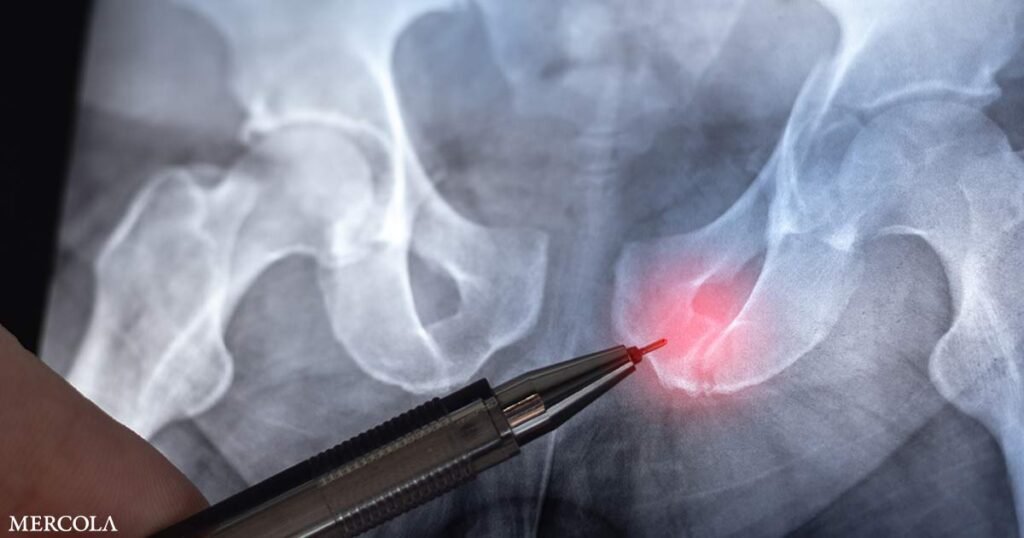

Hip Fractures from Osteoporosis Predicted to Double by 2050